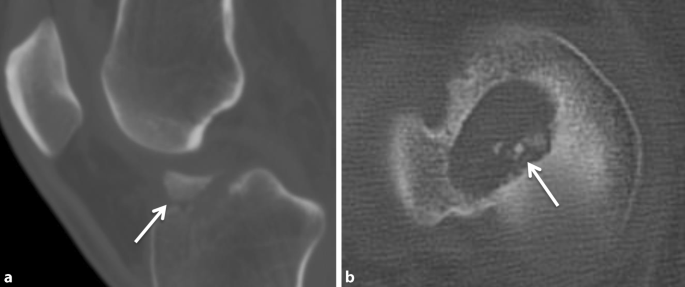

Die CT spielt für die präoperative Planung nach VKB-Plastik-Versagen eine bedeutende Rolle, um die Position, die Geometrie und das Kaliber der Bohrkanäle für die Revision zu beurteilen. Die Entscheidung zu einem Knochenaufbau in den Kanälen, besonders häufig bei der Double-Bundle-Technik, wird zumeist anhand der CT-Untersuchung getroffen. Des Weiteren ist im Vergleich zur MRT die Beurteilung von disloziertem orthopädischen Material in der CT besser, da die Metallartefakte deutlich geringer sind. Kleine knöcherne Ausrisse oder ossäre freie Gelenkkörper sind ebenfalls besser in der CT-Untersuchung zu erkennen (Abb. 5).

Abb. 5

figure 5

Die Computertomografie (CT) spielt eine bedeutende Rolle in der Abklärung von Avulsionsfrakturen nach Retrauma (Pfeil in a; Dislokation von Schrauben und Pins). Für die präoperative Planung wird die Weite des vorbestehenden Bohrkanals am besten in der axialen Ebene gemessen (b). Die hyperdensen Areale im tibialen Bohrkanal entsprechen Resten der bioresorbierbaren Polymerschrauben